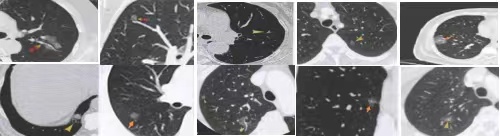

怎么才能知道肺结节是良性还是恶性?

人体肺部所患有的大多数疾病都会导致肺结节的形成,按照肺结节的基本疾病特性可将肺结节的病因分为……